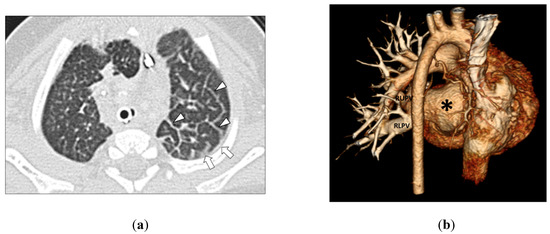

- Lee, E.Y.; Jenkins, K.J.; Vargas, S.O.; Callahan, R.; Park, H.J.; Gauthier, Z.; Winant, A.J. Thoracic multidetector computed tomography angiography of primary pulmonary vein stenosis in children: Evaluation of characteristic extravascular findings. J. Thorac. Imaging 2021, 36, 318–325. [Google Scholar] [CrossRef] [PubMed]

- Lee, E.Y.; Callahan, R.; Vargas, S.O.; Jenkins, K.J.; Park, H.J.; Gauthier, Z.; Winant, A.J. Extravascular MDCT findings of pulmonary vein stenosis in children with cardiac septal defect. Children 2021, 8, 667. [Google Scholar] [CrossRef]

- Lee, E.Y.; Vargas, S.O.; Jenkins, K.J.; Callahan, R.; Park, H.J.; Gauthier, Z.; Winant, A.J. Secondary pulmonary vein stenosis due to total anomalous pulmonary venous connection repair in children: Extravascular MDCT findings. Children 2021, 8, 726. [Google Scholar] [CrossRef] [PubMed]